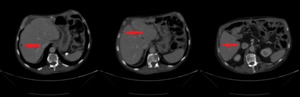

In February 2019, adjuvant chemotherapy with folinic acid, fluorouracil, irinotecan, and oxaliplatin (modified FOLFIRINOX) was initiated. About 2 months later, the serum laboratory test showed an increase in the level of the tumor marker, carbohydrate antigen (CA19.9) during chemotherapy (from 48.5 kU/l to 465 kU/l; normal range: <27.0 kU/L). In addition, a CT scan showed the appearance of 3 subcapsular lesions suspected to be metastases in the liver segment II and between liver segments V and VI (Figure 3). Thereafter, the patient received first-line palliative chemotherapy with nab-paclitaxel plus gemcitabine. A restaging with an abdominal MRI scan after 6 courses of chemotherapy showed a partial response manifested as a decrease in the size of the liver metastasis. No new lesions were detected. Furthermore, there was a progressive decrease of the CA19.9 level (from 465 kU/l to 55.2 kU/l) (Figure 4). Taking into consideration that the long-term survival of patients with AAC is usually improved as compared with PDAC patients and that radical surgery has been associated with favorable long-term survival, along with the patient’s motivation, we discussed the case in a multidisciplinary tumor board and decided for surgery of the liver metastasis.